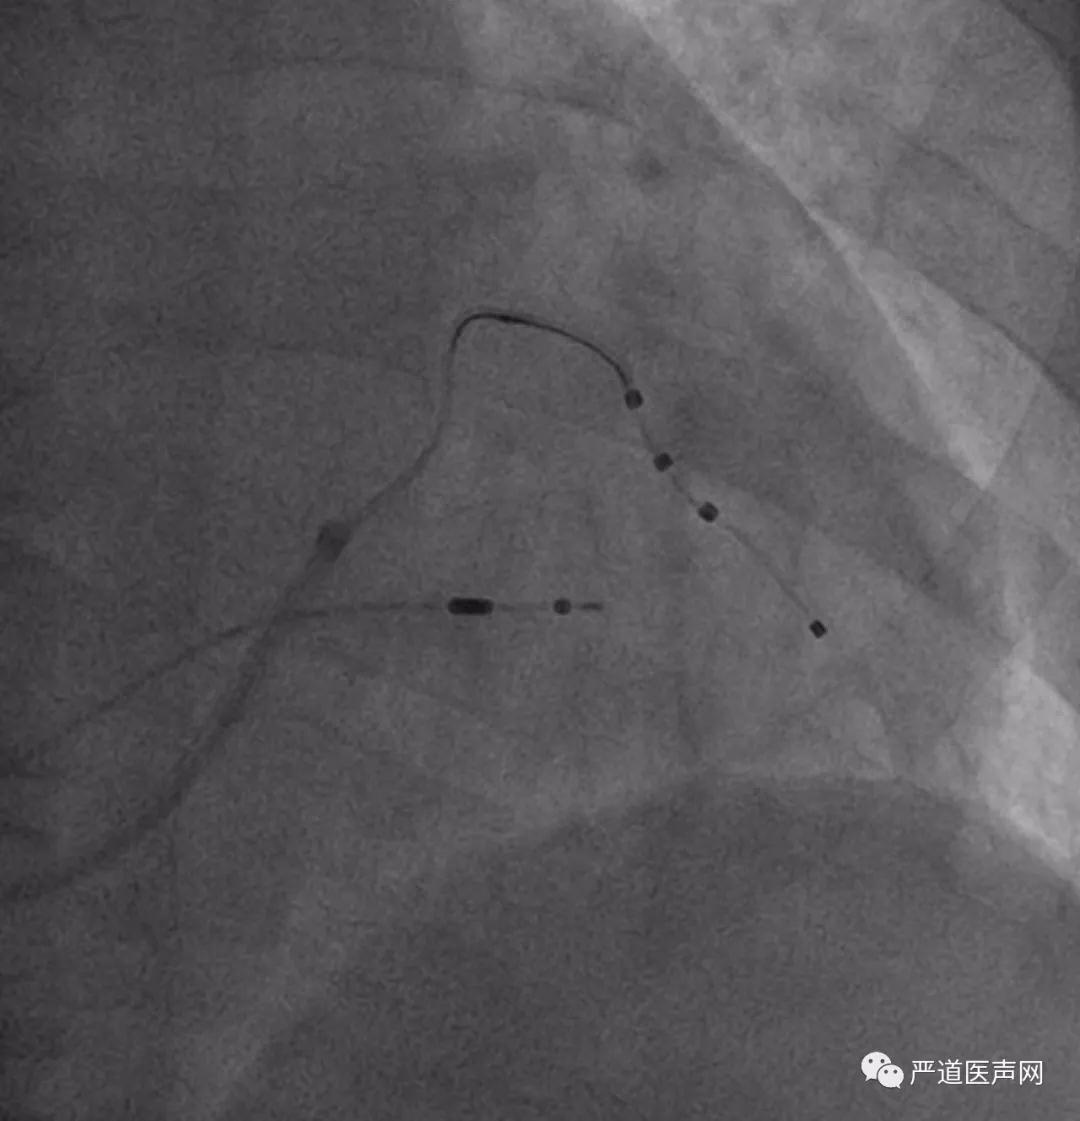

X4导线完全进入侧静脉

徐健教授提到,患者的血管条件不一样为植入操作带来的困难程度也各不相同,因此熟悉CRT植入相关的器械操作很重要,同时适当的手术策略转换也是必要的。

术后,徐健教授通过术中影像为学员们复盘了本例植入手术的全过程,学员们均表示本次培训班获益良多,不虚此行。